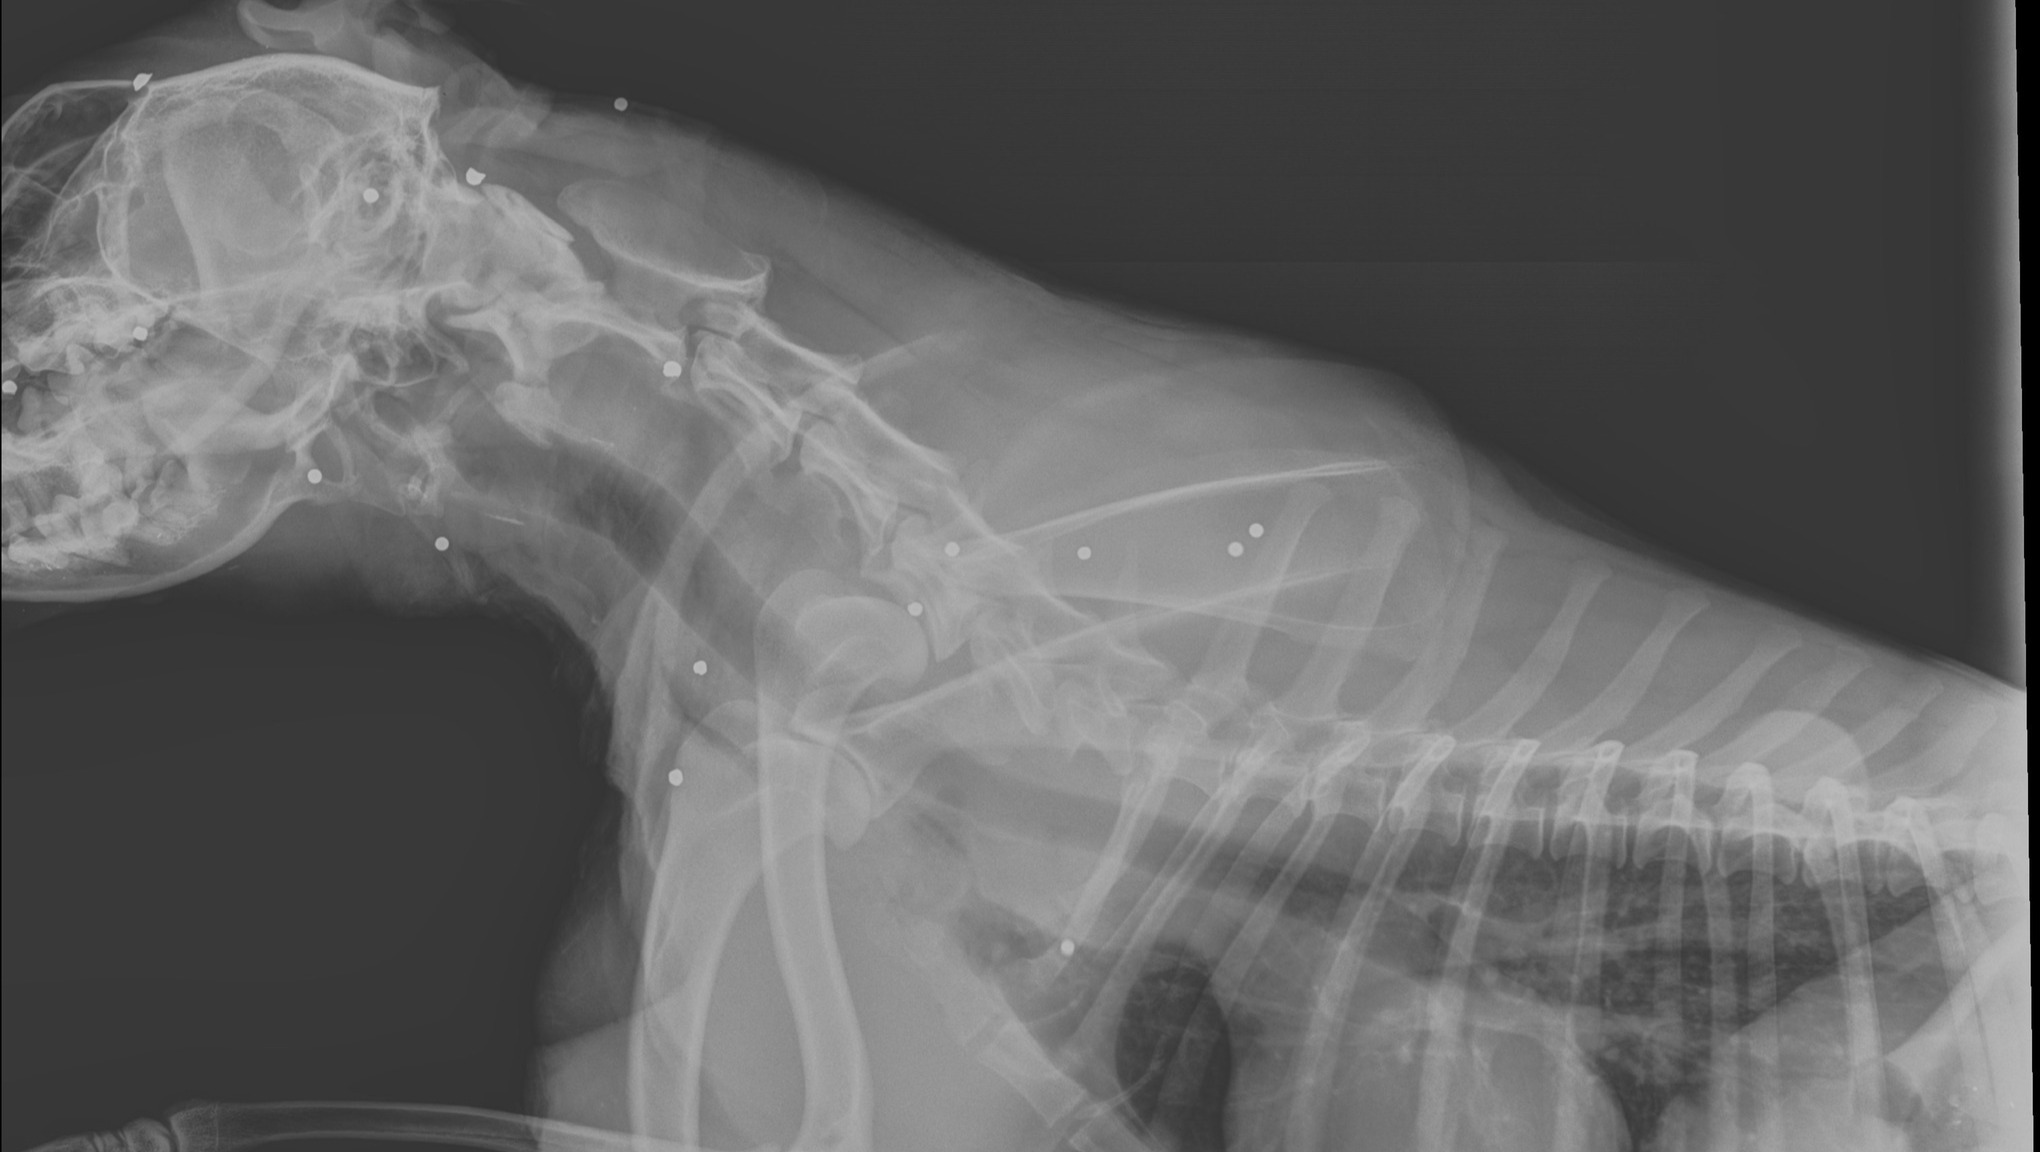

Here's the short version: Coco is a spunky lady, but has a herniated disc in her neck and is barely able to walk. She is also riddled with shotgun BB's from being shot during a hunt, which has made the diagnosis and treatment more difficult. Please read on if you'd like the full story, or donate if that is enough info for you! Thank you!!

Unfortunately, Coco was shot during a hunt in December 2023. While she did recover, she remains riddled with shotgun BB’s from nose to tail. The photo below is just a snapshot of what is in her.

- Coco cannot undergo an MRI due to the BB’s in her body.